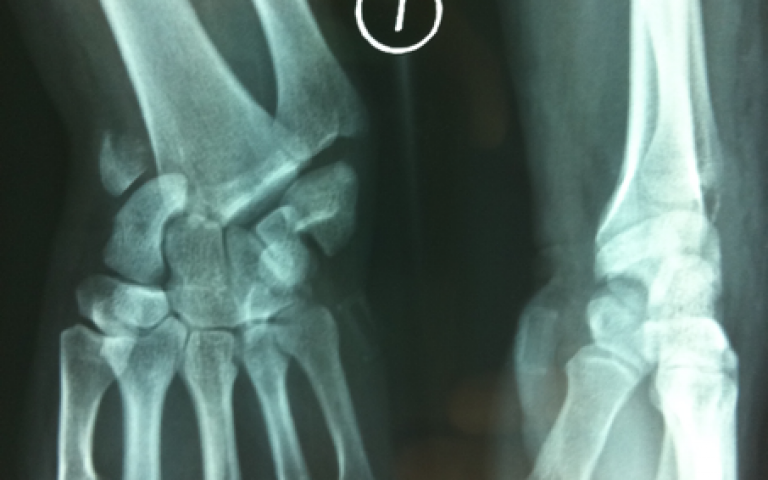

Hand and wrist emergencies Wrist fracture

Wrist fracture

Hand and wrist emergencies Scapholunate sprain

Scapholunate sprain

Hand and wrist emergencies Carpal dislocation

Carpal dislocation